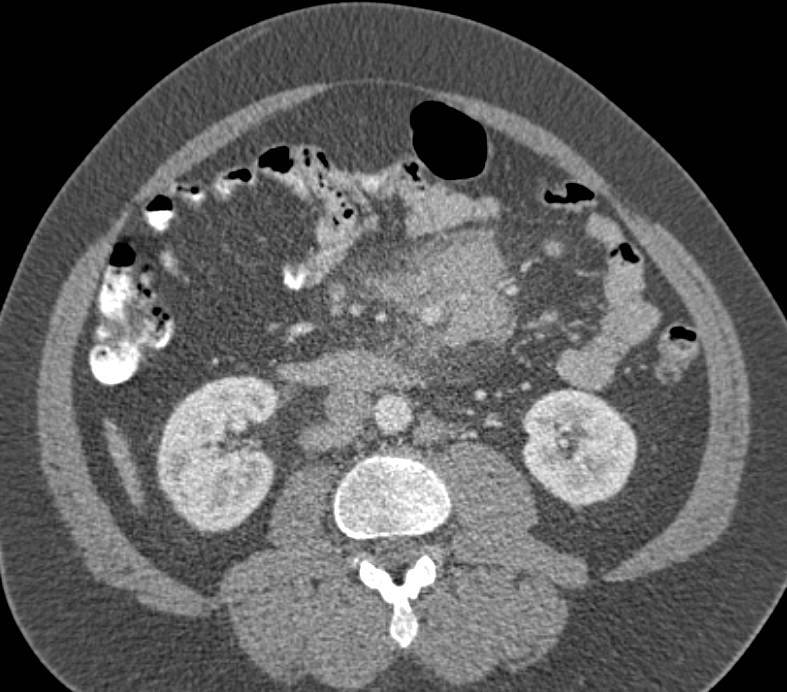

КТ ретроперитонеального фиброза: Изображения и диагностика